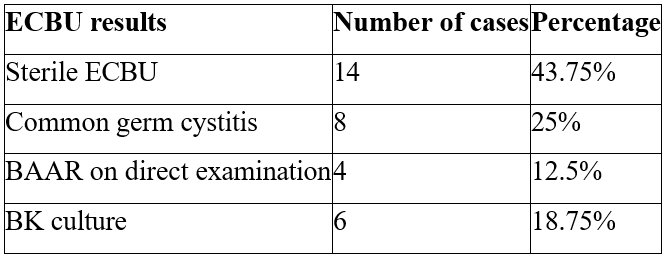

1/ ECBU: Urine was collected aseptically from morning urine, with fluid restriction for the preceding 12 hours. On 32 urine samples, direct examination and culture on specific media (LOWENSTEIN), carried out on 3 consecutive samples, gave the following results (Table 2):

Table 2: ECBU results.

In our series, BAARs were found on direct examination in 4 patients, and culture was positive for BK in 6. El Khader [8] found a positive ECBU in 5.2% of patients in his series of 57 patients. Proof of the tuberculous nature of urogenital lesions was obtained in 8.8% of cases on bacteriological grounds (5 times): isolation of BK in urine (3 times) and in abscess pus (2 times) [8].